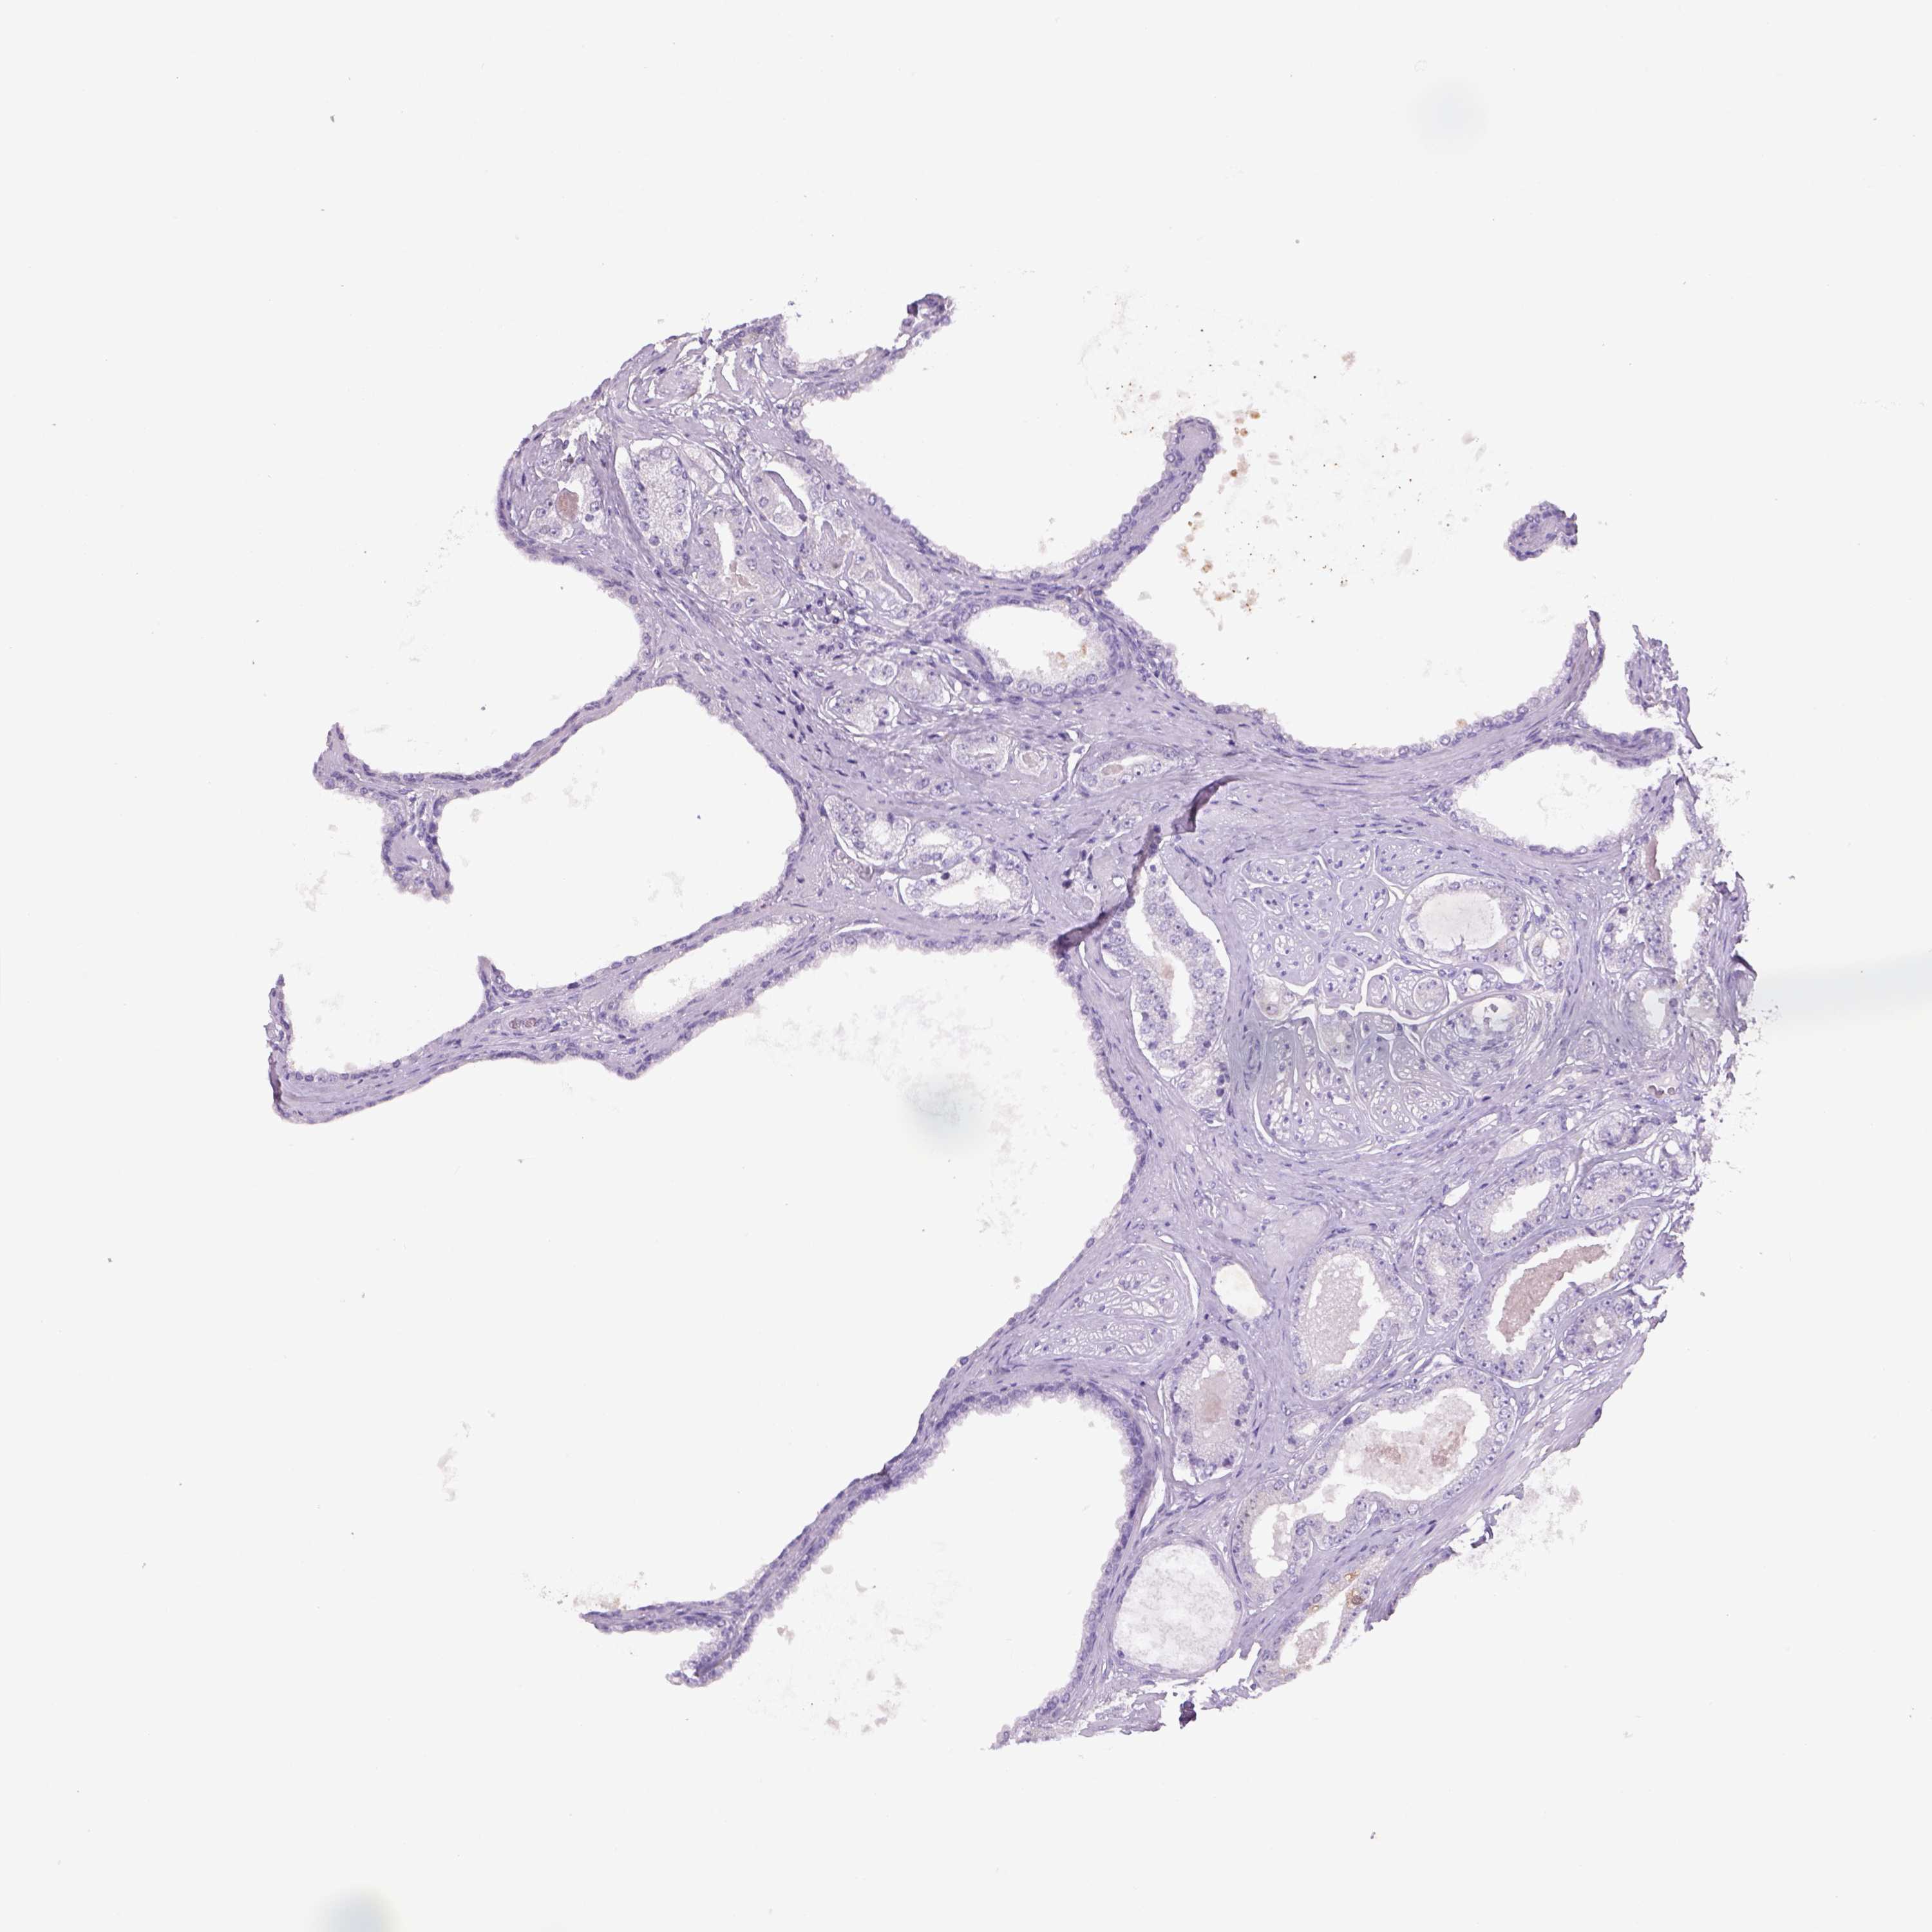

PROSTATE CANCER - Protein expressioni

A mouse-over function shows sample information and annotation data. Click on an image to view it in a full screen mode. Samples can be filtered based on level of antibody staining by selecting one or several of the following categories: high, medium, low and not detected. The assay and annotation is described here.

Antibody stainingi

Antibody staining in the annotated cell types in the current human tissue is reported as not detected, low, medium, or high, based on conventional immunohistochemistry profiling in selected tissues. This score is based on the combination of the staining intensity and fraction of stained cells.

Each image is clickable and will lead to virtual microscopy that enables deeper exploration of all samples and also displays staining intensity scores, fraction scores and subcellular localization as well as patient and tissue information for each sample.

Antibody HPA065419

Adenocarcinoma, High grade

Adenocarcinoma, NOS

Adenocarcinoma, Low grade